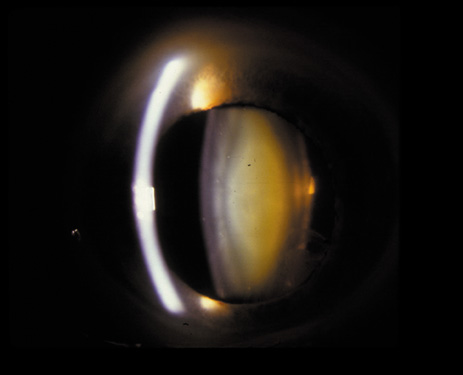

Nuclear cataracts tend to progress slowly. The refractive index of the lens changes as the nucleus progressively hardens, which usually results in increasing myopia.20,21 In some patients this is accompanied by optical distortion, especially of distant images, while near vision remains unaffected. A nuclear cataract is best seen with the narrow-beam direct illumination employed by the slit-lamp, which reveals the color and generalized haze or opalescence of the nucleus. In the early stages, the two halves (cotyledons) of the embryonic nucleus remain visible (Fig. 3). Later the entire nucleus appears as a homogeneous mass in contrast to the cortex (Fig. 4). Retroillumination may show the “oil droplet” effect (Fig. 5). Sometimes one may notice crystals in the lens nucleus (known as a Christmas tree cataract; Fig. 6A and B).

Fig. 4. Advanced nuclear cataract. Note the homogeneous nuclear opacity.